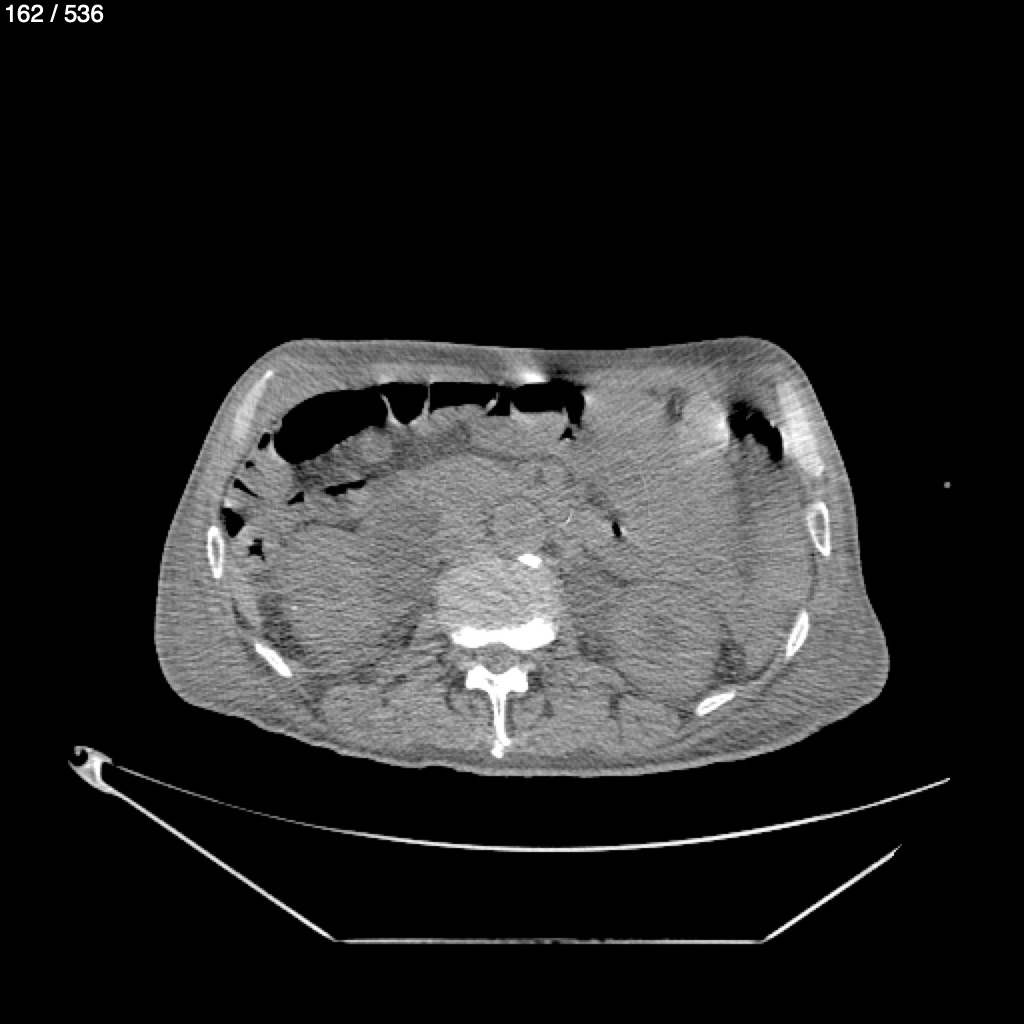

Angel Villalobos Palomeque 73 A - T.C Abdomen Simple